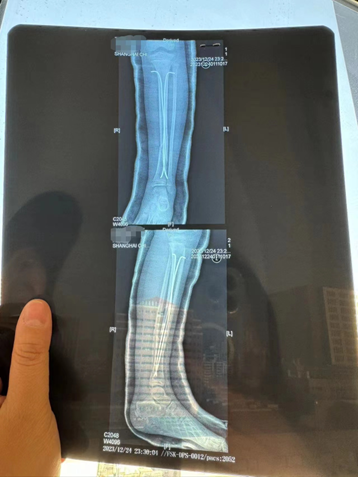

乐乐左腿植入了两颗髓内钉,目前只能躺在床上。陈丽娜摄

12月24日,这场意外刷屏了互联网,而这距离疯狂动物城正式开幕仅四天。孩子被送往医院后,左腿植入了两颗髓内钉,目前只能躺在床上。

乐乐被送到上海儿童医学中心后,门诊初步诊断为左腿胫骨骨折,并在当天做了6个小时的全麻手术,左腿里放置了两根髓内钉。

事发当日乐乐做了6小时全麻手术,左腿植入了两颗髓内钉。图源:受访者